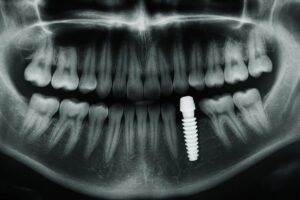

If you’re researching dental implants, this detailed review explains the procedures, benefits, and long-term care so you can make an informed choice. Whether you need one tooth or a full-mouth restoration, a trusted Golden Implant dentist in Cookeville, TN, can guide you through modern options and realistic expectations. Read on to learn how implants work, what to […]